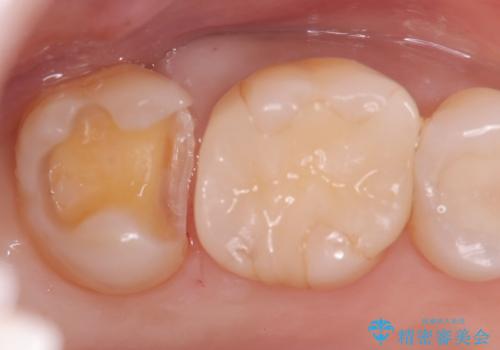

【セラミックインレー】定期検診で見つかった虫歯。

- 歯と歯の間で見つかりづらい虫歯でしたが、顕微鏡で確認し患者様に説明することで理解していただき、セラミックインレーにて修復治療を行いました。

以前にプラスチックの材料で修復した箇所が虫歯として見つかることはよくあります。

劣化の少ないセラミックインレーを選んでいただき、色調にも満足していただきました。